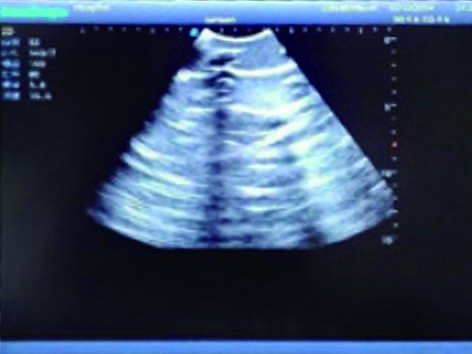

3)  Showing clear and real images of the tissues and organs (including muscle and connective tissue, air-containing lung tissue, pleural structure)